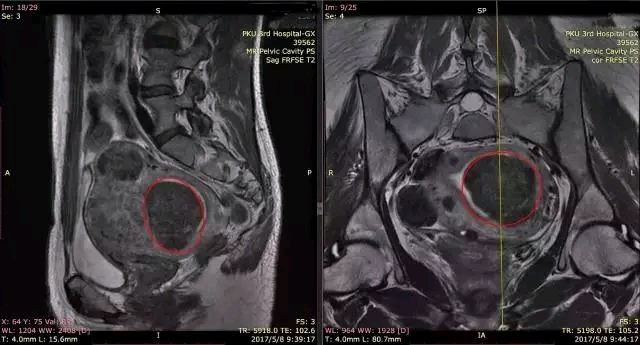

MRI的图像,不仅能从二维平面上直观的显示,还能结合其他的角度清晰的定位,图中红线部分为同一个子宫肌瘤

除了提供肌瘤的位置外,MRI还可以提供给我们很多别的信息,通常一个方向的T2加权序列会给我们提供大概26张甚至更多的图像,足够完整的显示子宫不同层面的情况,以及和周围的肠道、膀胱等组织脏器的关系,并且通过在T2加权下子宫肌瘤和子宫肌层信号的差异,能够初步判断这个子宫肌瘤是否适合我们目前开展的磁波治疗,如果是高信号(表示组织本身含水丰富或者血供丰富),那么做磁波治疗效果可能就不会太高,自然选择其他的方式就会更合适。